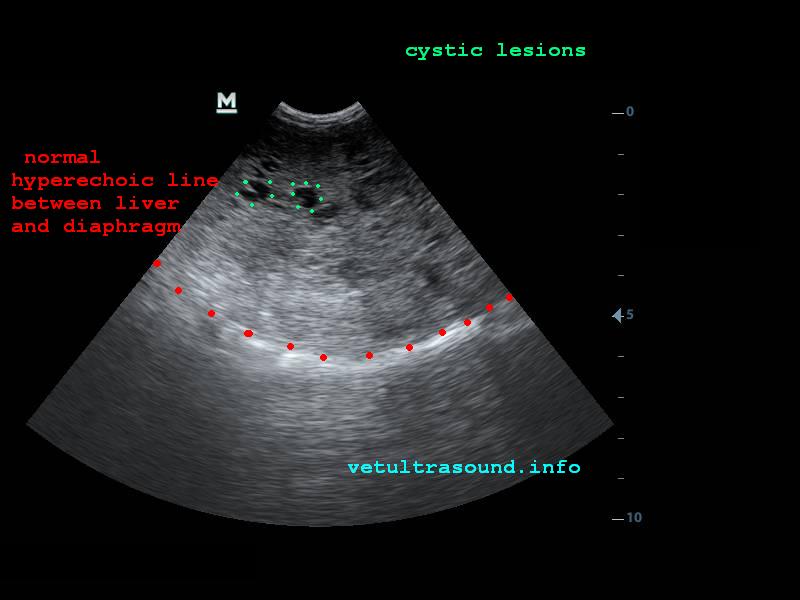

Στον υπέρηχο βρέθηκε ανομοιογένεια του ηπατικού παρεγχύματος, πολυάριθμοι κυστικοί σχηματισμοί οι οποίοι καταλάμβαναν κυρίως τον δεξιό πλάγιο λοβό του οργάνου(pic1&2). Η ροή του αίματος στη πυλαία φλέβα με τη βοήθεια του Pulse Wave Doppler βρέθηκε φυσιολογική(pic3), ενώ σε κλάδο της δεξιάς ηπατικής αρτηρίας ο δείκτης αγγειακής αντίστασης βρέθηκε μειωμένος(normal RI≈ 0.55)(pic4). Στοιχείο που μας δείχνει πως είτε η αγγείωση στη συγκεκριμένη περιοχή είναι νεόπλαστη, είτε λόγω χρόνιας νόσου ο διάμεσος ιστός που περιβάλλει τα αγγεία έχει χάσει την σκληρότητά του. Μικρή ποσότητα ασκιτικού υγρού βρέθηκε ανάμεσα στις εντερικές έλικες. Χωρίς παθολογικά διογκωμένους λεμφαδένες εκτιμήθηκε η κοιλιακή κοιλότητα(pic5). Οι υπόλοιπες δομές ελέγχθηκαν χωρίς παθολογικά ευρήματα.